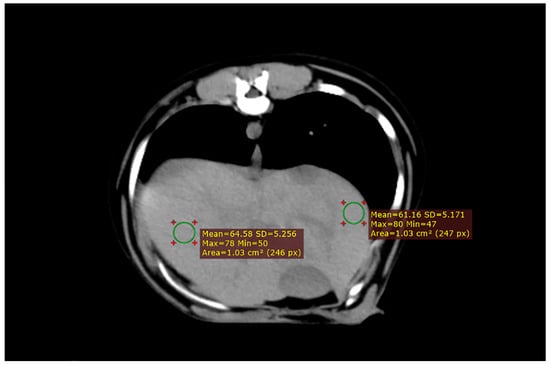

Animal positioning and CT scan results are shown in Figure 2. The dogs were placed on the examination bed in an anesthetized state. Both forelimbs were pulled forward and the chest was placed against the examination bed with the median sagittal plane perpendicular to the examination bed. The examination site was fed into the scanning frame. Six sampling frames were consecutively placed in the left and right liver lobes once the CT scan was completed. The sampling frame avoided the gallbladder and large blood vessels.

Figure 2. CT scan results. After completion of the CT scan, six sampling frames were placed on each side of the liver. It was important to avoid major blood vessels and bile ducts when placing the sampling frame to prevent measurement errors.